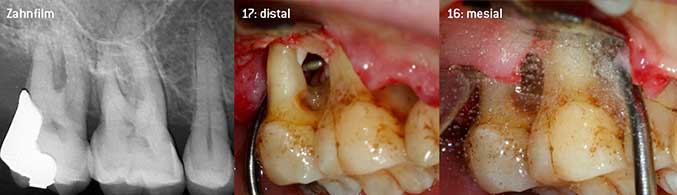

Als Initiatoren zur Entwicklung der neuen diamantierten Luftscaler-Spitze 3AP sahen es beide Zahnärzte als notwendig an, die Einschränkung in der Handhabung bisher kommerziell vermarkteter diamantierter Spitzen insbesondere während der Furkationstherapie oder in engen Knochentaschen zu verbessern. Dies sollte unabhängig von nicht-chirurgischem (Abbildung 2) oder chirurgischem Vorgehen sein (Abbildung 3).

Geschlossenes Debridement der Furkationen an 26 und 36

Abb. 2: Geschlossenes Debridement der Furkationen an 26 und 36 bei fortgeschrittenem Attachmentverlust

(Fotos Abb 2 -4: © Dr. Chr. Graetz)